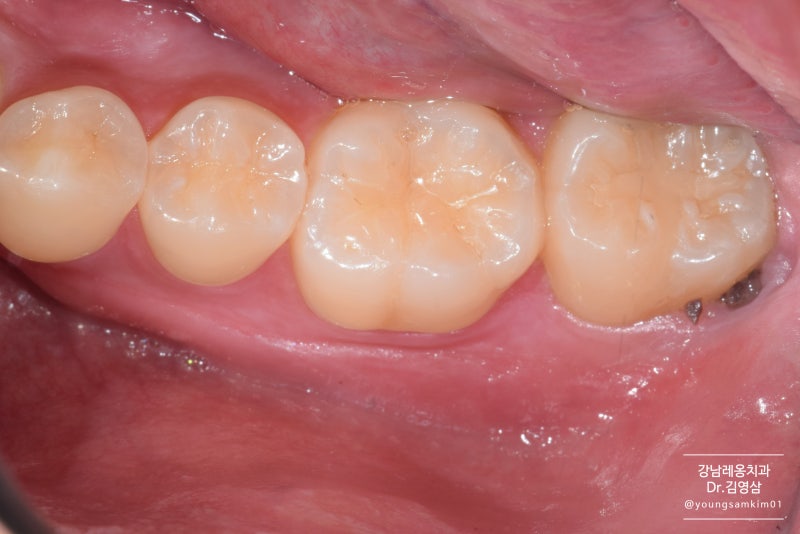

왼쪽의 사랑니와 오른쪽의 앞니. 사랑니 옆에 뿌리가 녹아 짧아지는 것을 보셨나요? 발치가 전혀 아깝지 않은 것이 현 상황입니다. 발치 후 엑스레이 사진입니다. 추출된 공간은 여전히 비어 있습니다. 염증이 없고 잇몸뼈의 상태가 양호하면 발치 당일 임플란트 식립이 가능하나, 이 경우 임플란트가 잘 고정되지 않아 실패할 확률이 높습니다. 사람마다 다르지만 뼈가 완전히 채워지는 데는 일반적으로 1~2개월 정도 걸립니다. 그 기간 동안 환자의 잇몸 상태가 좋지 않아 잇몸 치료를 시작하기로 했습니다. 환자가 항상 알아야 할 것은 치아를 오래 사용하기 위해서는 잇몸이 건강해야 한다는 것입니다. 노화가 진행됨에 따라 잇몸의 노화 과정이 서서히 사라집니다. 잇몸이 건강하면 치아를 지탱하는 잇몸뼈도 건강하기 때문에 잇몸이 좋지 않은 상태에서 치주치료를 지속하는 것이 좋습니다. 재생치료도 잇몸치료와 동시에 진행됩니다. 치아는 송곳니와 어금니 사이에 틈이 있기 때문에 “웃을 때 치아 사이 틈이 보여서 신경이 쓰인다”고 합니다. 수지가 벗겨지고 변색됩니다. 레진을 접착제로 붙이는 과정이기 때문에 칫솔질, 음식물 섭취 등 외부 자극에 의해 색이 진해지거나 사라질 수 있습니다. 다만, 치아가 빠지더라도 발치하지 않고 재수술이 가능하나, 레진치료 후 재수술 비용이 발생하게 됩니다. 공간이 자연스럽게 채워지나요? 위에서 언급한 것처럼 변색과 벗겨짐이 걱정된다면 교정이나 보철로 치료하는 것이 가장 좋다. 치아 사이가 벌어져 고민이시라면 치과에 내원하셔서 전문의와 상담을 받으시는 것이 좋습니다. 레진 전후 비교는 이제 2개월이 되었습니다. 잇몸뼈가 꽉 차 있는지 엑스레이를 찍었습니다. 2개월 전과 비교하면 다행히 뼈가 많이 자랐다. 이제 임플란트 식립이 가능해 당일 식립이 가능합니다. 치근에 해당하는 임플란트 픽스쳐만 식립합니다. 정확한 각도, 깊이 및 위치에 앵커를 설치하는 것이 중요합니다. . 누가 그렇게 좋아. . ^^ 잇몸뼈 상태가 좋지 않은 환자분들은 특히 힘듭니다. 이렇게 되기까지 약 2개월을 기다린 끝에 임플란트 헤드를 들어올리기로 결정했습니다. 2개월 후 치은골이 임플란트와 잘 맞는 것을 확인하고 최종 수복을 하였다. 방금 식립했을 때와 비교하여 X-ray 촬영 결과 주변 치은골이 잘 부착되고 단단해졌습니다. 첨부된 사진은 이식된 크라운의 사진입니다. 크라운 모양도 잘 되어있어요^^ 그리고 가운데 동그란 구멍도 똑같이 보이시죠? 이 구멍에는 임플란트의 뿌리와 헤드를 연결하는 작은 나사가 임플란트에 삽입됩니다. 임플란트 문제로 인해 보철물이 흔들리는 경우 이 구멍을 사용하여 임플란트를 조이는 나사를 조이거나 교체합니다. 임플란트 전보다 오른쪽 치아를 사용할 수 있어 오른쪽에서 편안하게 식사를 할 수 있어 마음이 편하다고 한다. 또한 환자가 몸이 좋지 않은 경우 염증이 이미 증가한 경우가 많습니다. 궁금하신 사항이 있으시면 언제든지 강남리온치과의원으로 연락주시기 바랍니다. 오늘도 좋은 하루 보내시길 바랍니다.서울시 서초구 강남대로 415 대동빌딩 4층 강남리온치과의원